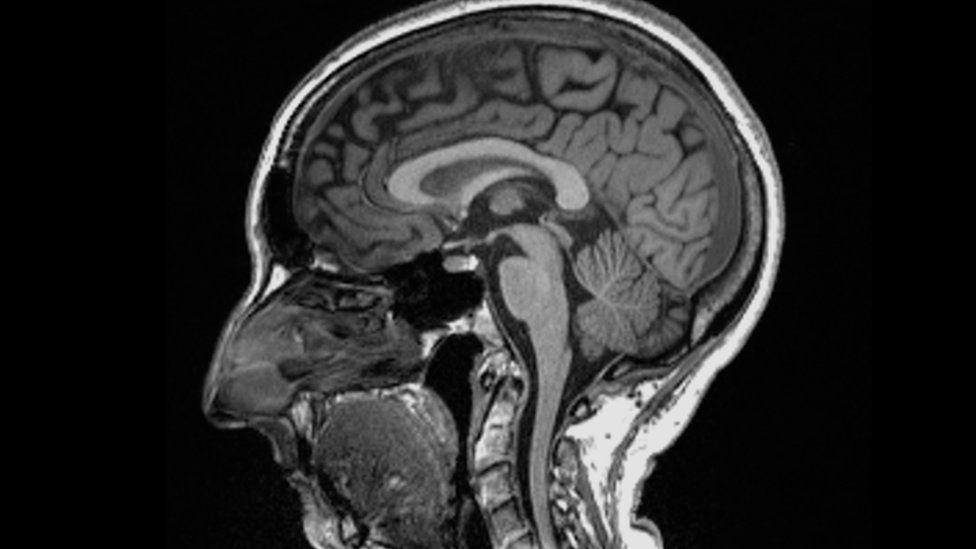

Africa-Press – Rwanda. Catching Covid may cause changes to the brain, a study suggests. Scientists found significant differences in MRI (magnetic resonance imaging) scans before and after infection.

Even after a mild infection, the overall size of the brain had shrunk slightly, with less grey matter in the parts related to smell and memory. The researchers do not know whether the changes are permanent but stressed the brain could heal. The study is published in the journal Nature.

They found: The overall brain size in infected participants had shrunk between 0.2 and 2% There were losses in grey matter in the olfactory areas, linked to smell, and regions linked to memory

The most significant loss of grey matter was in the olfactory areas – but it is unclear whether the virus directly attacks this region or cells simply die off through lack of use after people with Covid lose their sense of smell.